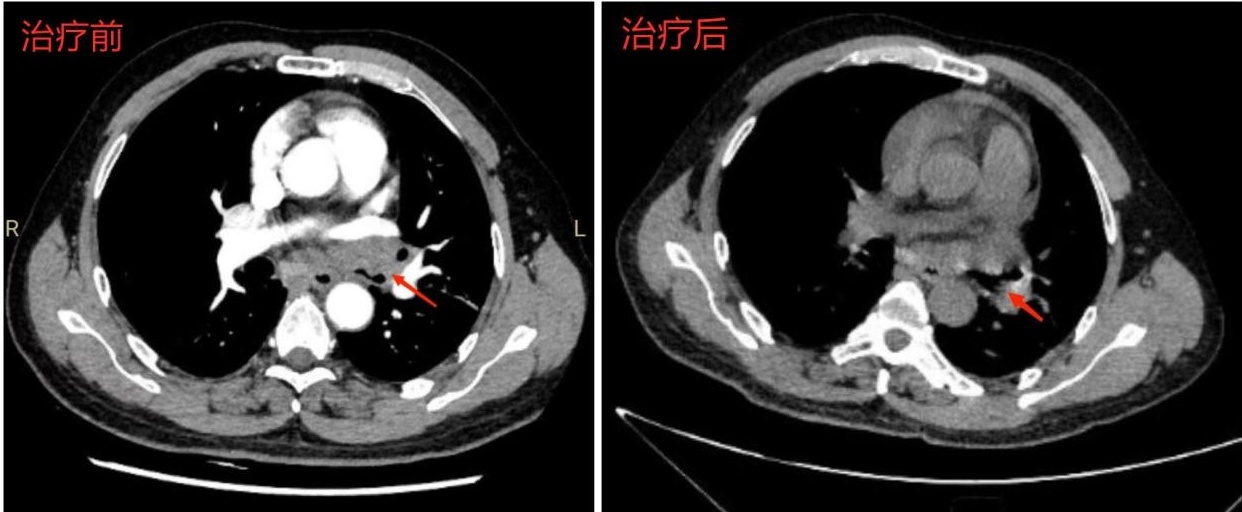

4月29日,在麻醉科、泌尿外科、手术室和内镜中心护理团队的配合下,全麻状态下硬质支气管镜和奥林巴斯1T150软镜结合进入左主支气管中段,左主支气管远端可见宽基底新生物近乎完全阻塞左主支气管。在泌尿外科副主任医师王二鹏的现场指导下,全麻状态下硬质支气管镜植入左主支气管中段,左主支气管远端可见宽基底新生物近乎完全阻塞左主支气管。启动钬激光,选择钬激光功率自 20-40W逐渐升高对肿瘤组织进行消融切割,协同应用活检钳清理。经过30分钟激光消融和清理治疗,突入到左主支气管及左、下叶管腔内的肿瘤组织基本清理干净,管腔通畅。术后患者气喘症状明显缓解。

患者男性,50岁,确诊晚期肺腺癌(ALK阳性)8月余,经靶向治疗后病灶曾有吸收好转,4月18日因气喘进行性加重,再次收治市二院呼吸与危重症医学科综合病区。复查胸部CT和气管镜显示左肺门肿块突入左主支气管及左上、下叶支气管管腔,导致左主支气管管腔重度狭窄。如不积极给予处理,左主支气管一旦完全阻塞后,发生左全肺不张将加重患者呼吸困难,给后续治疗增加很大风险。